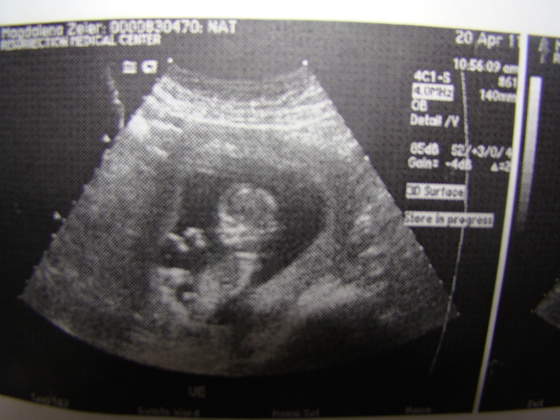

Lena ale sliczny brzuszek :-) a dzidziuś jak ślicznie zapozował do zdjęcia! ja mam tylko zdjęcie plecków bo się nie dał namówić na pozowanie :-) może na następnym mi buźke pokaże